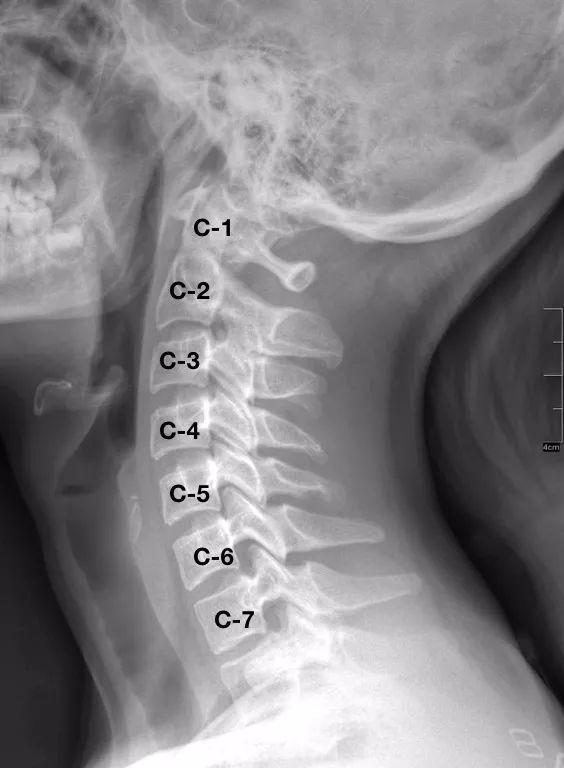

Exames de Imagem: O raio-x pode ser usado para avaliação da estrutura óssea da coluna, também para pesquisar possíveis instabilidades. A tomografia computadorizada (TC) é preferida principalmente para se observar a estrutura óssea da coluna cervical, como nos casos de traumatismos (acidentes), enquanto a ressonância magnética (RM) é indicada para visualização dos discos intervertebrais, ligamentos, músculos, raízes nervosas, nervos, plexos e medula espinhal.